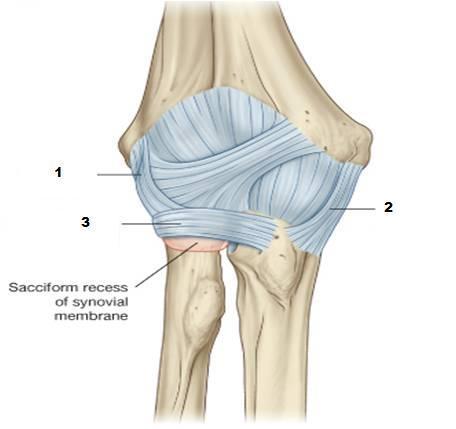

Describe the anatomical position of the collateral ligaments of the elbow joint